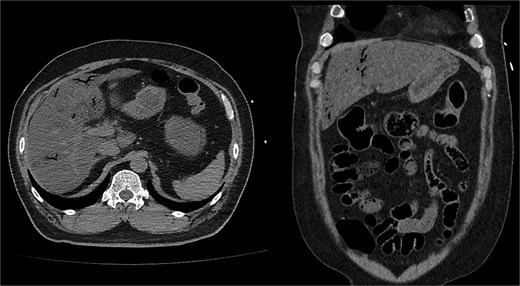

Noncontrast abdominopelvic computed tomography (CT) showed multifocal air foci within the liver and mesenteric vessels, suggesting possible bowel ischaemia (Fig. 1). After surgical consultation, medical management was recommended as DKA was considered the primary cause. The patient was admitted to the intensive care unit (ICU) for DKA management.

Noncontrast abdominopelvic CT revealed multifocal air foci in the liver and mesenteric vessel, suggesting portal vein and mesenteric vein gas.